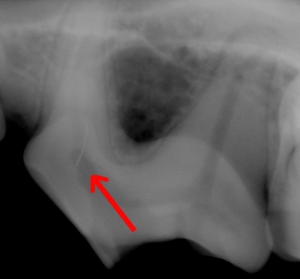

● 歯の破折 1:歯髄治療が適応である破折法

歯の破折方向が地面に対して平行です。このような場合には、虫歯の治療を行うことで今後の再発を防げます。このような割れ方をした場合には、積極的に治療を行い、後に生じる根先膿瘍を予防することが必要です。

● 歯の破折 2

このような破折を起こした場合、歯髄の治療を完璧に行ったとしても、破折部位が歯肉に到達しているために、歯肉辺縁から深部への菌の侵入が予想されます。このような場合、①抜歯 ②前述の方法と同様の歯髄治療。のいずれかが選択されますが、裂肉歯とは「噛む」ことに重要であるために、当院の場合、①の抜歯を選択することはきわめてまれになります。

こちらは破折した歯が接着したままであるために、歯髄が露出しているかどうかが不明な症例です。レントゲンにて確認し、深部に到達しているかどうかを確認します。![]()